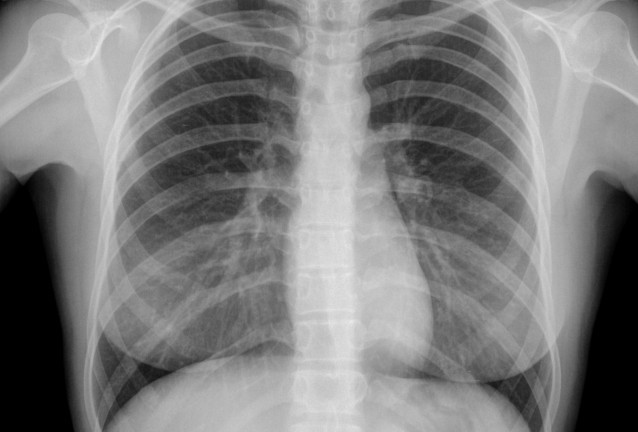

Ракът на белия дроб представлява растеж на променени клетки в белите дробове, които се делят много по-бързо от здравите клетки и групирайки се образуват тумор. Повечето типове рак на белия дроб нарастват бавно и често минава дълго време преди да се проявят симптомите. Тъй като е обичайно ракът на белия дроб да метастазира доста рано, в повечето случаи той бива диагностициран едва, когато ракови клетки са се появили на други места в организма.

Има два основни вида рак на белия дроб - дребноклетъчен и недребноклетъчен рак на белия дроб (НДКРБД), въз основа на това как изглеждат раковите клетки, видяни под микроскоп. НДКРБД съставлява около 80% от всички случаи на рак на белия дроб. Основните симптоми на рака на белия дроб са: кашлица, която не изчезва; задух или хриптене по време на дейности, които преди са извършвани лесно; пресипнал глас; отделяне на кръв при кашляне; загуба на апетит или нежелана загуба на тегло, без видима причина; повтарящи се пристъпи на бронхит; болки в гърдите, гърба и ръцете.